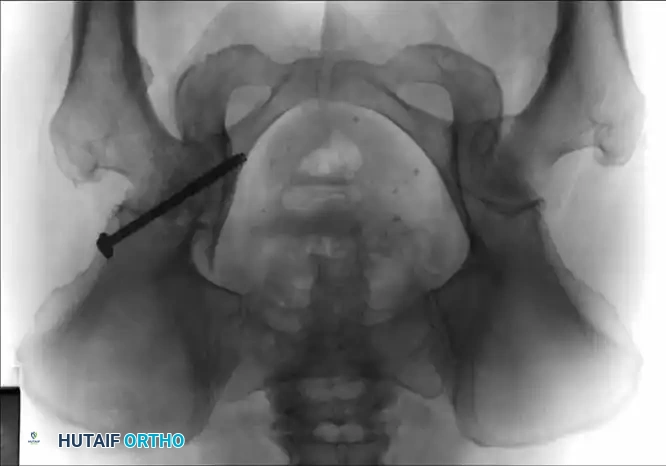

Associated Surgical & Radiographic Imaging

Hutaifortho's Orthopaedic Diagram